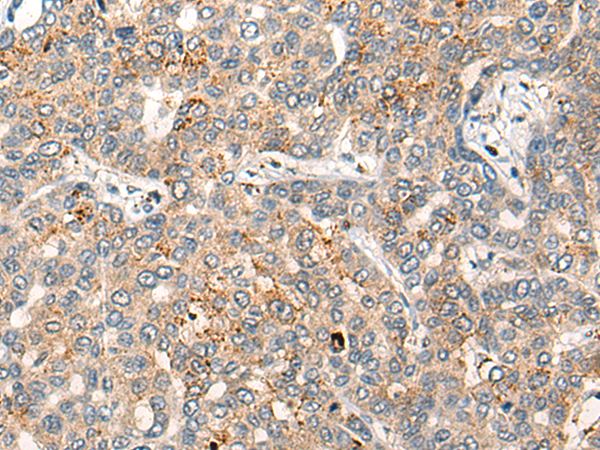

分类: 科研抗体货号: P13129别名: AMID; PRG3应用: IHC反应种属: Human, Mouse